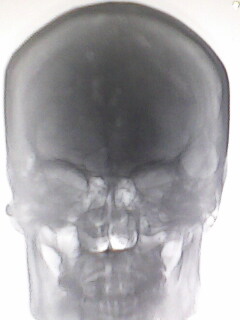

患者,女性,外伤,拍摄头颅正侧位片,侧位未见异常,正位颅骨见不规则多发低密度区,正常吗?

蛛网膜颗粒压迹可能,建议必要时ct。女性骨髓瘤少见,且颅骨主要表现为弥漫性骨质疏松。

蛛网膜颗粒压迹可能性大,请必要时ct。

蛛网膜颗粒压迹,建议必要时ct。女性骨髓瘤少见,且颅骨主要表现为弥漫性骨质疏松。

另加嗜酸性肉牙肿待排!